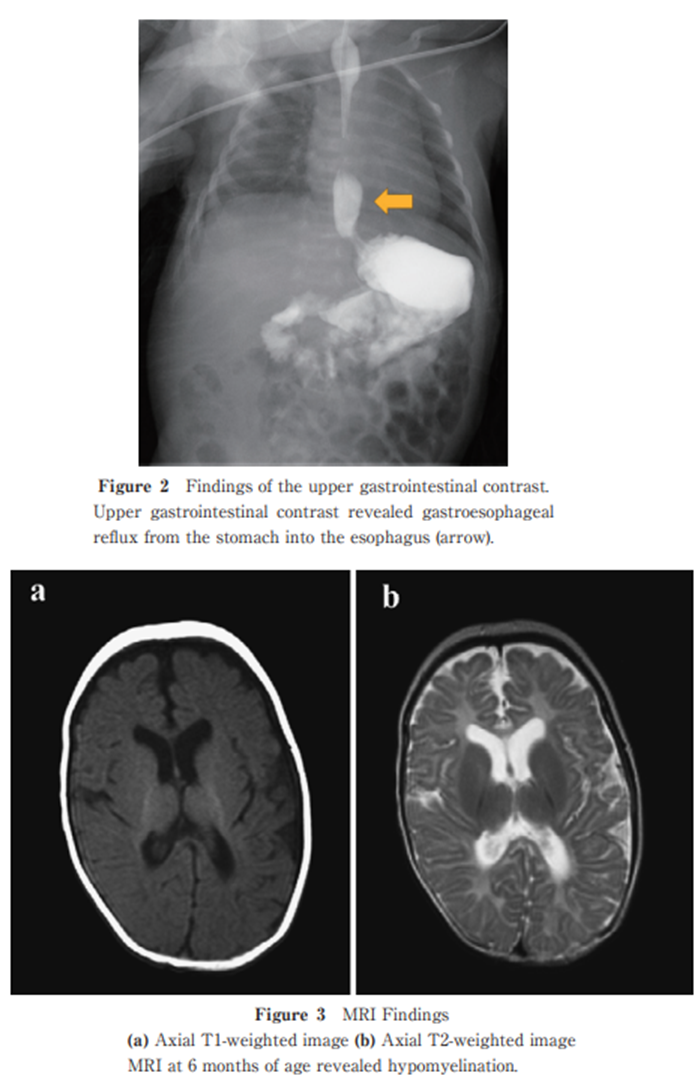

Novel Variants in AARS1-related White Matter Disease: A Case Report

https://doi.org/10.51040/dkmj.2023-054

Susumu Sasaki et al.

Published online : December 26 , 2024